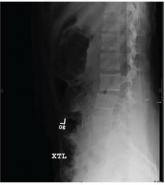

A 63-year-old woman is transferred to your facility for evaluation of acute lower extremity paralysis. She has had ongoing back pain for the past seve...